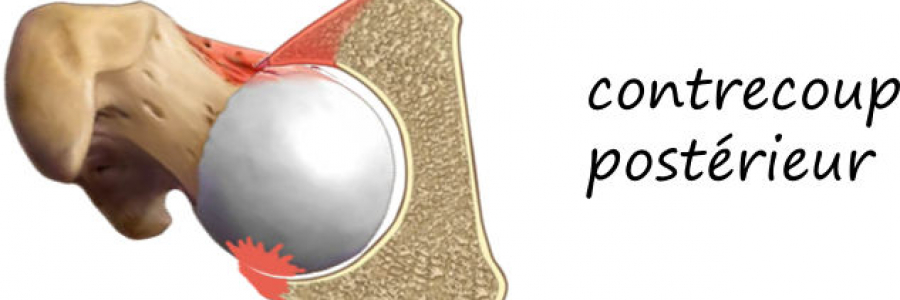

De plus le contact prématuré du col avec le cotyle décentre la hanche et provoque une lésion postérieure « de contrecoup », ce qui explique aussi le caractère arthrogène du conflit fémoro-acétabulaire.